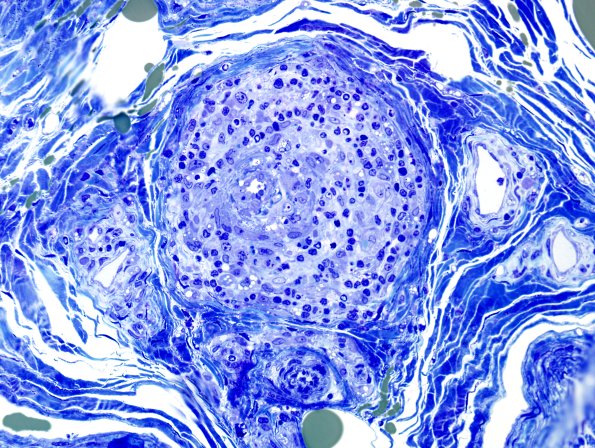

Washington University Experience | PERIPHERAL NEUROPATHY | 11 VASCULITIS - VASCULOPATHY | 3 Vasculitis - NOS | 27D2 Vasculitis (Case 27) Plastic 2

Examples of both fibrotic and inflamed vessels are shown. (plastic sections) ---- Not shown: Neurofilament immunoreactivity shows marked axon loss similarly in all fascicles.